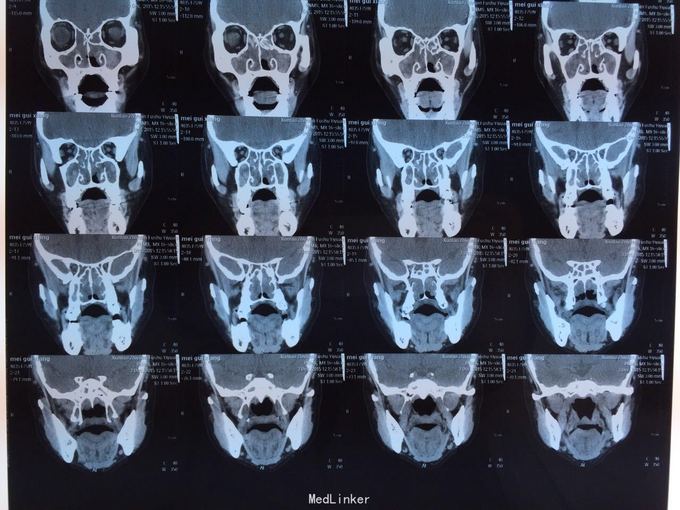

患者鼻塞分泌物增多,一年余,自诉曾于03年及09年两次鼻息肉摘除手术,现查鼻内镜双侧鼻腔可见大量息肉样物,鼻窦ct示全组鼻窦炎,鼻腔息肉。患者拟住院行第三次鼻息肉手术。